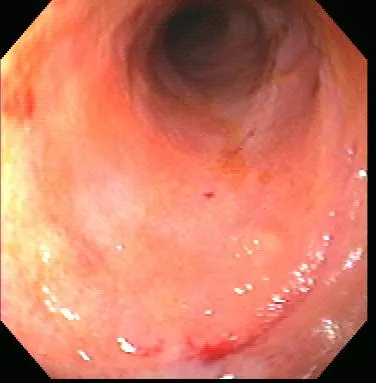

Gastroenteroscopy revealed a hard plastic foreign body (Figure 2) with curved, pointed ends. Points of the object were embedded in the gastric antral mucosa, resulting in hyperplasia. One of the curved points extended through the pylorus and hooked into the proximal duodenum (Figure 3). The endoscope could be passed around the foreign body into the duodenum, allowing biopsy of the duodenal mucosa. The gross appearance of the duodenal mucosa was normal (Figure 4). Attempts to remove the foreign body endoscopically were unsuccessful. Before the dog was sent to surgery for removal of the foreign body, colonoscopy was performed. The colon appeared normal on gross inspection (Figure 5). Biopsies were obtained from the cecum; ascending colon; transverse colon; and proximal, middle, and distal descending colon. At surgery, a gastrotomy incision was made in the pyloric antrum and the foreign body was forcefully removed. It was a plastic object used to secure the legs of a turkey carcass.

Healthy descending colon